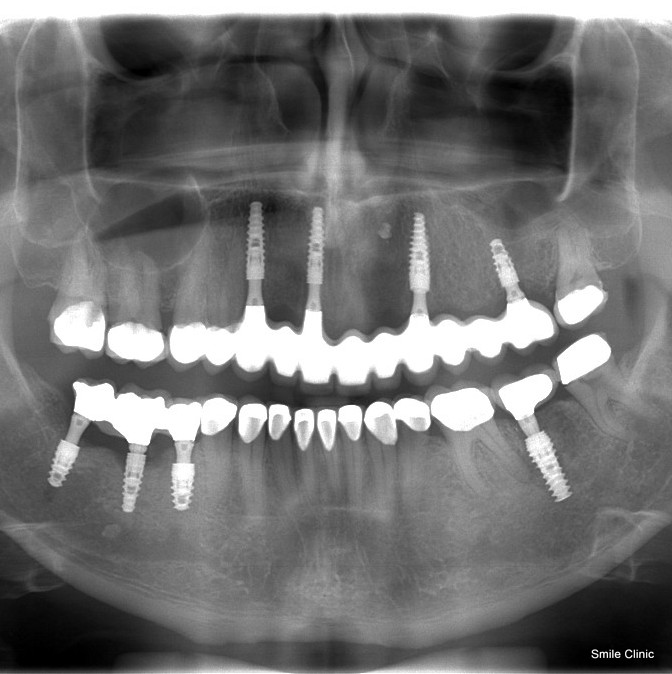

Ian from the Liverpool area in the UK had a dental consultation with his dentist, and forwarded us the notes so that we could make a quote & treatment plan comparison for him.

Ian immediately decided to come over to us and start treatment – 14 dental crowns and 8 dental implants. This is what Ian had to say about his “smile journey” through dental holiday:

I decided after doing much homework and research that the best place to visit was the Smile Clinic in Slovakia, after an initial consultation, they gave me a number of options. In just over 3 months I have gone from an embarrassing smile to a confident smile.